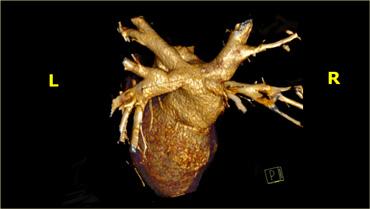

Tái tạo 3D cho thấy tiểu nhĩ trái (mũi tên xanh) và động mạch vành trái (mũi tên vàng) sau khi đã loại bỏ tiểu nhĩ trái. A=trước, S=trên

Khi đánh giá các động mạch vành, cần loại bỏ tiểu nhĩ trái để có thể quan sát được động mạch mũ trái (LCX) và đoạn gần của động mạch liên thất trước (LAD).